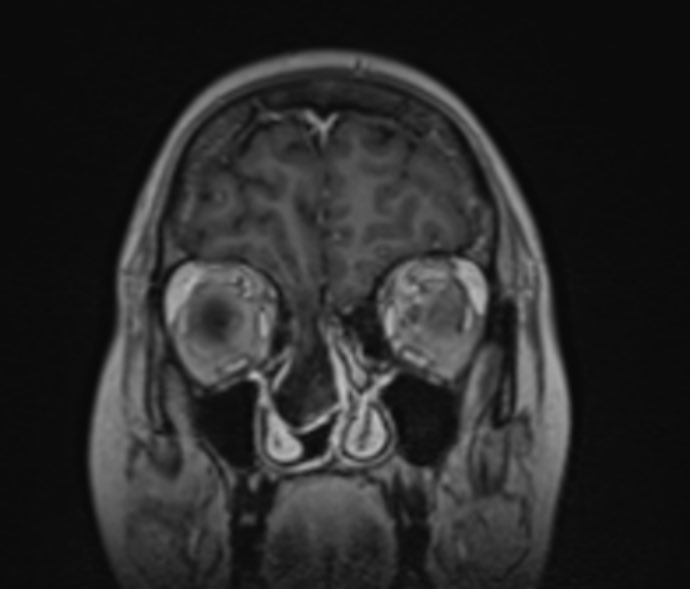

🔍 Case of the Day | The Value of MRI in Recurrent Meningitis A 29-year-old female presents with recurrent episodes of meningitis, without prior trauma or surgery. Clinical suspicion: occult anterior skull base defect. 🩻 MRI Brain: • Cribriform plate defect measuring 9.8 ×…